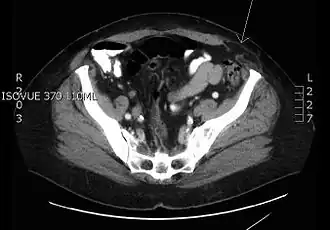

Hernia spiegeli op de plaats van de pijl.

Een hernia spiegeli, soms gespeld hernia spigeli (of laterale ventrale hernia) is een hernia door spiegelse fascie. Deze fascie is de aponeurose (het peesblad) tussen de musculus rectus abdominis (de rechte buikspier) mediaal en de linea semilunaris (zie afbeelding) lateraal. Deze hernia's ontwikkelen zich meestal onder de linea semicircularis (de onderrand van de dorsale zijde van de rectusschede) omdat daar het weefsel minder steun heeft. Een hernia spiegeli ontwikkelt zich meestal niet tot aan het subcutane vet, maar blijft pariëtaal, dat wil zeggen tussen de spieren. Hierdoor is de hernia aan de buitenkant vaak niet goed zichtbaar. Doordat de breukpoort vaak klein is heeft deze hernia een grote kans in te klemmen met strangulatie, verstoring van de bloedtoevoer naar de breukinhoud, tot gevolg.

Patiënten presenteren zich gewoonlijk met wisselende zwelling ter plaatse, pijn lokaal of tekenen van darmobstructie.[1] Met echografie of een CT-scan kan de diagnose worden bevestigd.